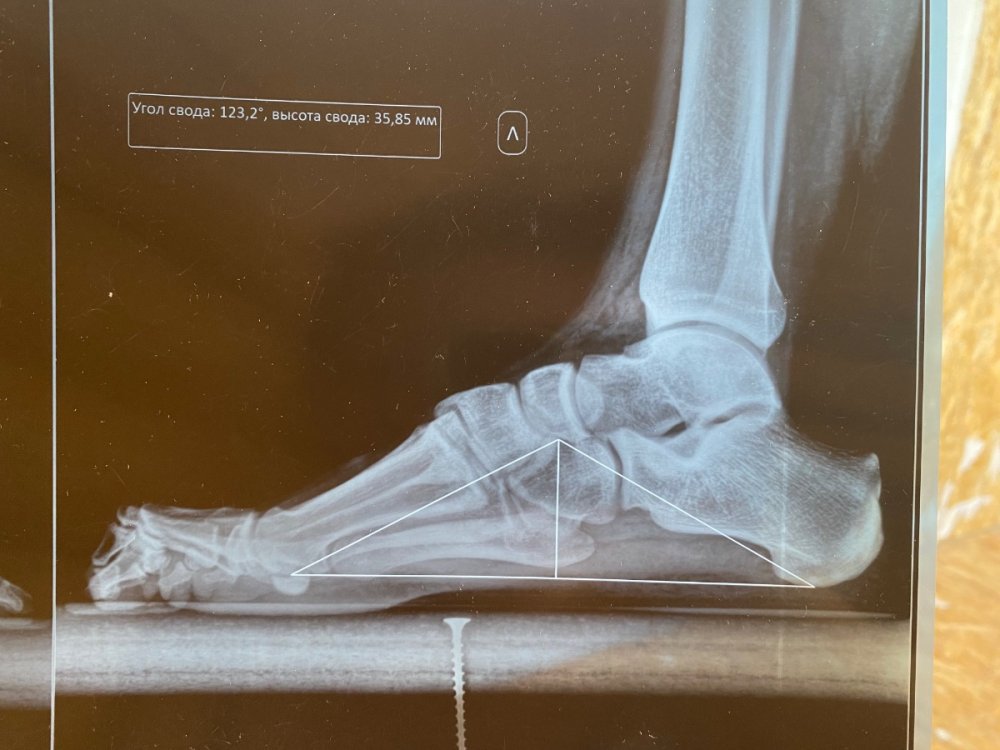

Добрый день! Проходил обследования в гос. учреждениях и платных больницах, был выставлен диагноз «молоточкообразная контрактура пальцев обеих стоп; высокосводчатая стопа». В военкомате был направлен на подтверждение диагноза в областную больницу, где был выставлено иное заключение (на фото). Также прикрепил результаты рентгена. На какую категорию годности я могу претендовать сейчас?

IMG_1209.jpeg

IMG_1210.jpeg

IMG_1212.jpeg

IMG_1214.jpeg

IMG_1207.jpeg